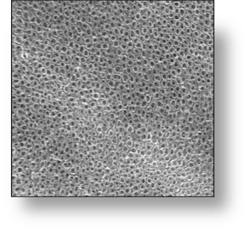

Nasseo’s proprietary nanotube implant technology is the result of over 10 years of research and development at the UC San Diego Bioengineering and Materials Science Departments and the Bio-Implant Laboratory at Lund University in Sweden. The research has resulted in over 15 scientific publications and a wealth of unpublished data. Nasseo has successfully integrated this nanotechnology into the TiArray™ Dental Implant system, hoping to address the lack of soft tissue connection and inflammation problems that plague current standard of care dental implants.